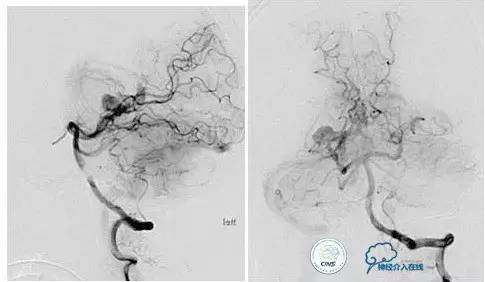

小脑幕缘区DAVF,颈外动脉和颈内动脉的供血支均非常细小。

Marathon微导管进入分支后,在主干血管内放置Hyperform球囊。

最终的栓塞结果。